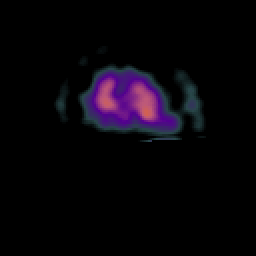

Subacute Stroke, overlay -- Slice #23

[Home][Help][Clinical] Slice 23